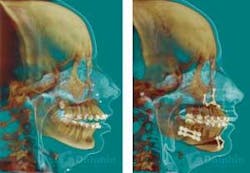

3-D volumetrics can be combined with 3-D photography that melds the surface rendering of the cone beam scan with the dentofacial soft tissue information of the photograph. Bony and soft tissue landmarks can be recorded and studied in a 3-D environment. The traditional cephalometric analyses are based on a two-dimensional system. The advent of new software applications (such as Dolphin 3-D®) will revolutionize the evaluation of dentofacial and skeletal growth and development, and change the future of orthodontic and orthognathic treatment-planning (see Figure 7).